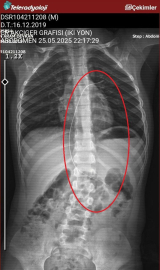

Şırnak’ta yaşayan Semra (37) ve Mehmet Ötün (40) çiftinin oğulları Aram Devran Ötün, mayıs ayında piknikteyken salatalık parçası yuttuktan sonra öksürük ve kusma şikayetleri görülünce Şırnak Devlet Hastanesi’ne götürüldü. Burada çekilen röntgen ve MR’da Aram’ın vücudunda kateter unutulduğu görüldü. Diyarbakır’daki Gazi Yaşargil Eğitim ve Araştırma Hastanesi Kadın Doğum ve Çocuk Ek Binası’na sevk edilen Aram, 5,5 saat süren riskli bir ameliyata alınarak 18 santimetre uzunluğundaki kateter çıkarıldı. Ameliyat sonrası yapılan incelemelerde kateterin kalp kapakçığına ve ciğerlerine zarar verdiği belirlendi.

Oğlunun piknikte salatalık parçası yuttuktan sonra sürekli öksürmeye ve kusmaya başladığını söyleyen Semra Ötün, “Çocuğum 3 yıl önce Steven Johnson sendromu hastalığına yakalandı. Milyonda bir görülen antibiyotikten kaynaklı bir hastalık. Doktorlar öyle söyledi. Bizi acilen Diyarbakır Dicle Üniversitesi Çocuk Hastanesi bölümüne sevk ettiler. 1 ay yoğun bakım sürecimiz oldu. 28 gün yoğun bakımda, 3 günde serviste kaldı. Damar yolundan, kasıktan serum taktılar. Kateter denilen tel çocuğun vücudunda bırakılıyor. Biz taburcu olduğumuzda fark edilmiyor. 3 yılın sonunda biz bunu fark ettik. Pikniğe gittik. Oğlum salatalık parçası yuttu ve salatalık parçasından sonra akşama kadar öksürdü. Hiçbir şekilde durmadı. Kusuyordu. Ben şüphelenmeye başladım. Çocuğum normal değildi. Sonra eşime danıştım. Akşam 21.00 civarında acile götürdük. Röntgeni ve MR’ı çekildi. Tuhaf bir şey olduğunu anladık. Doktor röntgeni gösterdi. Tel kalmıştı. Çok kötü bir şekilde. Acil doktoru film çektikten sonra bize bir tel parçasını gösterdi. Bizi bekletmeden Diyarbakır’a sevkimizi verdiler. Diyarbakır Gazi Yaşargil Eğitim ve Araştırma Hastanesi Kadın Doğum ve Çocuk Ek Binası’na gittik. Çocuğun kasıklarından anjiyo yolu ile teli çıkaracaklarını ama riskli bir ameliyat olduğunu söylediler. O süreçte çocuk gerçekten sürekli yoruluyordu. İkide bir oturuyordu. ‘Anne çok yoruldum, karnım ağrıyor’ diyordu. Ben ağrı kesiciler ile geçiştirmeye çalışıyordum. Bu telin 3 yıl boyunca çocuğumda kaldığını öğrendim. Ailece yıkıldık” diye konuştu.